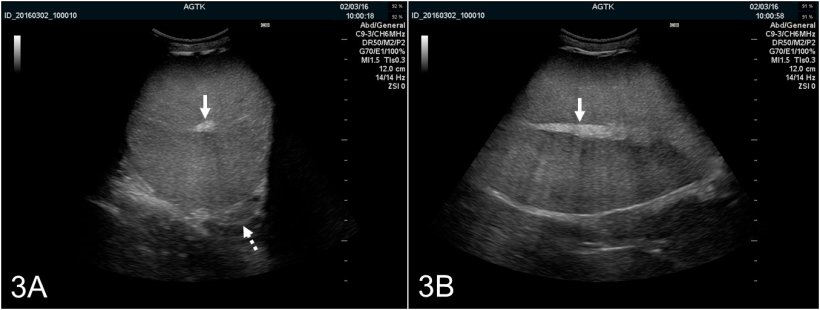

Los testículos se pueden escanear longitudinalmente o transversalmente (figura 2A y B). Para determinar la circunferencia del testículo, se deben emplear imágenes transversales. El tejido testicular sano tiene una ecogenicidad media y presenta una  ecotextura homogénea, con el rete testis hiperecogénico en el centro del testículo (figura 3A y B).

Figura 3: Imágenes ultrasonográficas del testículo de un verraco explorado transversalmente (A) y longitudinalmente (B). El rete testis se representa como una mancha hiperecogénica en el centro del testículo (flecha sólida). El parénquima testicular presenta ecogénicidad media y de ecotextura homogénea. La imagen transversal también proporciona una visualización óptima del corpus epididimal (flecha punteada), que es normalmente de apariencia ultrasonográfica similar a la del testículo.